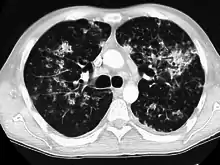

Diffuse

The diffuse pattern typically refers to GGOs in multiple lobes of one or both lungs. Broadly, a diffuse pattern of GGO can be caused by displacement of air with fluid, inflammatory debris, or fibrosis. Cardiogenic pulmonary edema and ARDS are common causes of a fluid-filled lung. Diffuse alveolar hemorrhage is a rarer cause of diffuse GGO seen in some types of vasculitis, autoimmune conditions, and bleeding disorders.[6]

Inflammation and fibrosis can also cause diffuse GGOs. Pneumocystis pneumonia, an infection typically seen in immunocompromised (e.g. patients with AIDS) or immunosuppressed individuals, is a classic cause of diffuse GGOs. Many viral pneumonias and idiopathic interstitial pneumonias can also lead to a diffuse GGO pattern. Radiation pneumonitis, a side effect of pulmonary radiation therapy, can lead to pulmonary fibrosis and diffuse GGOs.[6]

CT image showing crazy paving pattern of ground-glass opacities in both lungs.